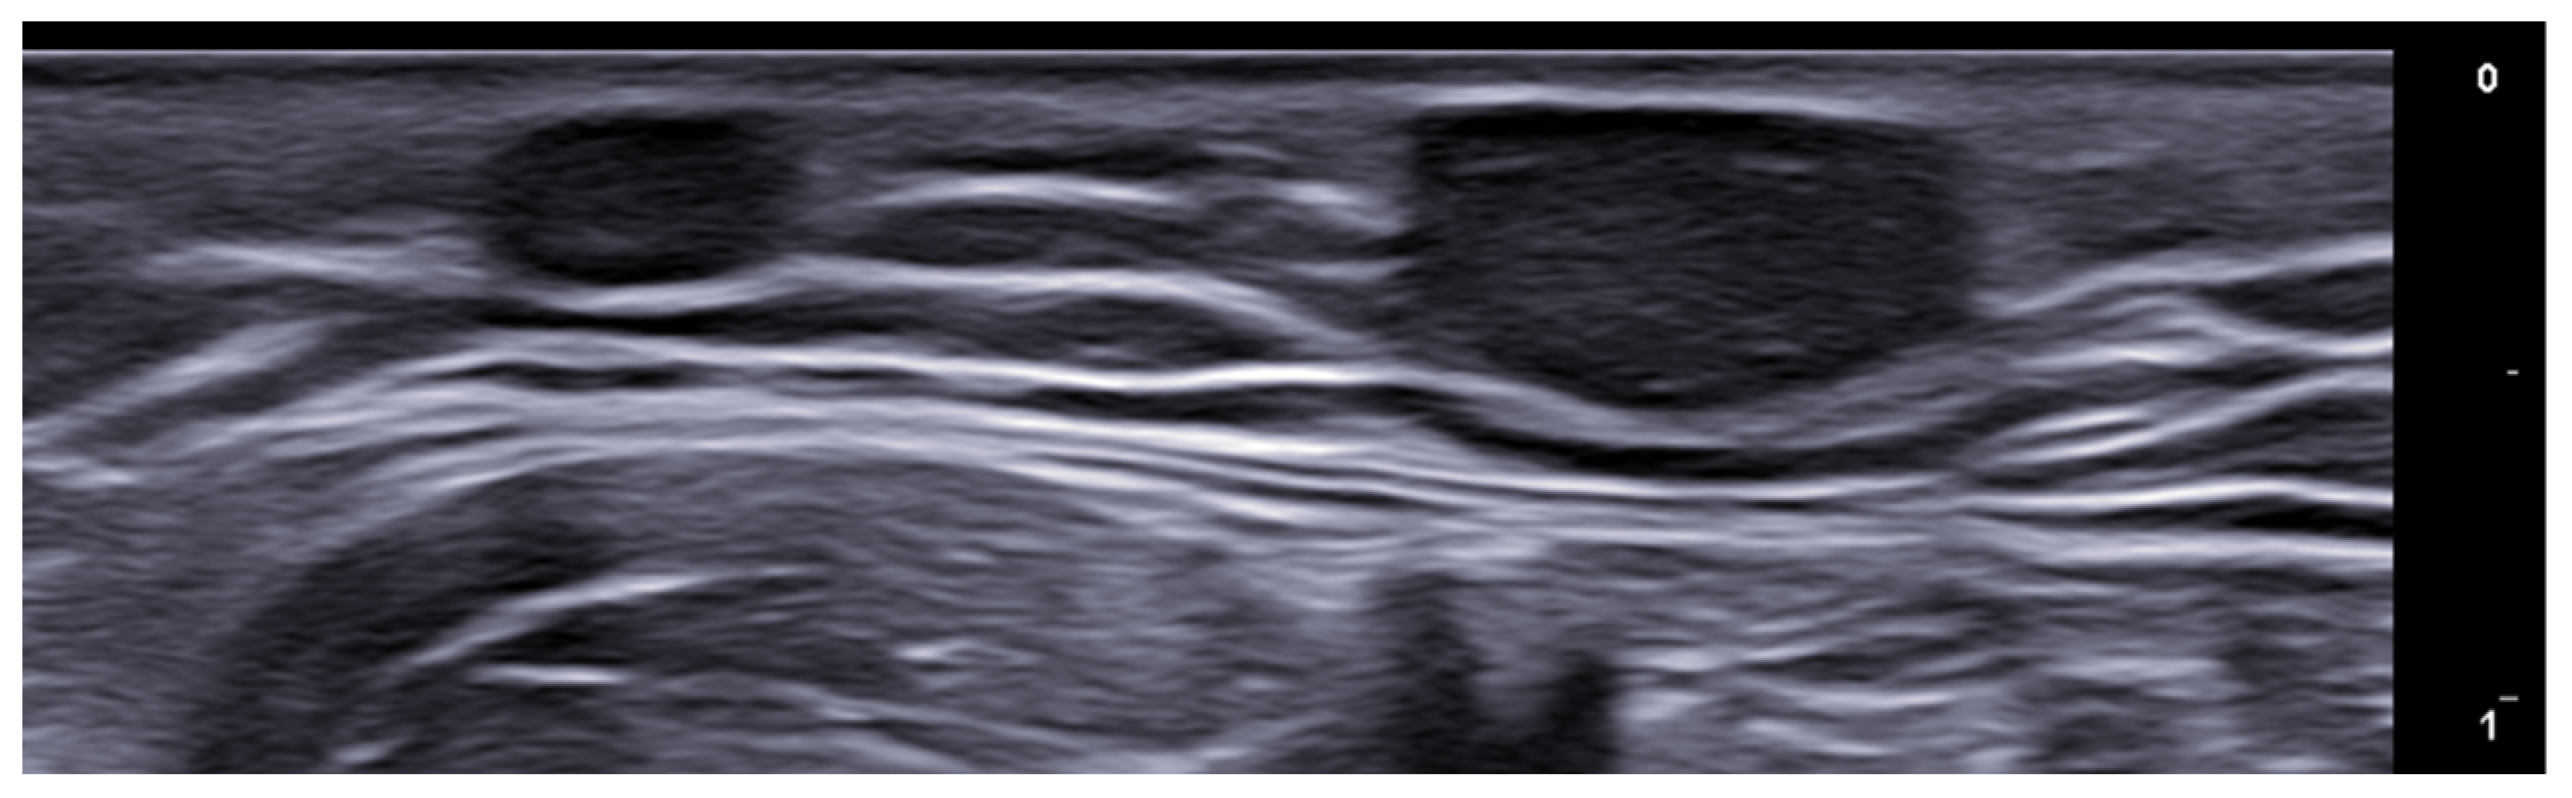

- Berritto, D.; Iacobellis, F.; Rossi, C.; Reginelli, A.; Cappabianca, S.; Grassi, R. Ultra high-frequency ultrasound: New capabilities for nail anatomy exploration. J. Dermatol. 2017, 44, 43–46. [Google Scholar] [CrossRef]

- Szymoniak-Lipska, M.; Polańska, A.; Jenerowicz, D.; Lipski, A.; Żaba, R.; Adamski, Z.; Dańczak-Pazdrowska, A. High-Frequency Ultrasonography and Evaporimetry in Non-invasive Evaluation of the Nail Unit. Front. Med. 2021, 8, 686470. [Google Scholar] [CrossRef]